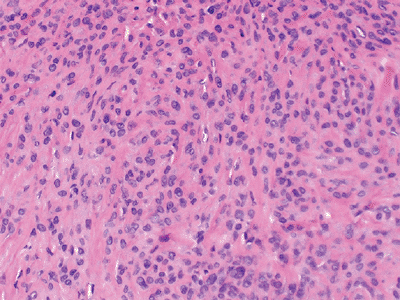

Myxoid component is characterized

histologically by mixture of lipoblasts and uniform nonlipogenic

mesenchymal cells in prominent myxoid stroma associated with a fine

capillary network (Fig. 12-2). -

Round cell component is characterized histologically by more cellular regions of round cells (see Fig. 12-2).

![]() |

|

Figure 12-2 (A)

Myxoid liposarcoma. Mixture of lipoblasts and uniform nonlipogenic mesenchymal cells in prominent myxoid stroma associated with a fine capillary network. (B) High-grade myxoid liposarcoma with a predominant round cell component. |